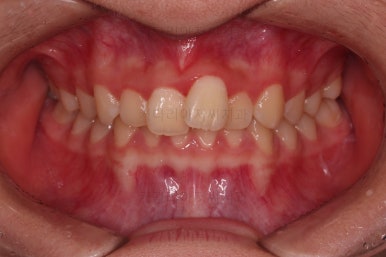

1. 초진

초진 시 입안의 모습입니다.

눈에 띄는 부분은 당연히 앞니가 삐뚤고, 앞니 하나가 앞으로 튀어나온 모습인데요.

자세히 관찰해 보면 다른 문제점들이 보입니다.

우선 위아래 앞니가 깊숙히 맞물려 있는 과개교합 양상인데요.

깊게 맞물려 있으면 기능적으로도 좋지 못하고 입술의 볼륨감에도 부정적이며 치아도 많이 마모가 되기 쉽습니다.

✅ 앵글씨 2급 부정교합

이번 환자분은 앵글씨 2급 부정교합이었는데요.

정상교합에 비해서 윗니가 상대적으로 앞에 아랫니가 상대적으로 뒤에 위치한 부정교합이 앵글씨 2급 부정교합입니다.

거꾸로 아랫니가 앞에 위치한 부정교합은 앵글씨 3급 부정교합입니다.

이번 환자분은 어금니가 위아래가 지그재그 서로 엇갈려 꽉 끼이는 교합이 아니라 1대1로 치아가 부딪혀 있는 상태였습니다.

이런 경우는 치아가 마모가 매우 잘되고 치아의 잇몸 근처 부분이 빨리 패여져 나가거나 잇몸 퇴축도 빨리 오게 됩니다. 물론 씹는 기능도 떨어지게 마련이고요.